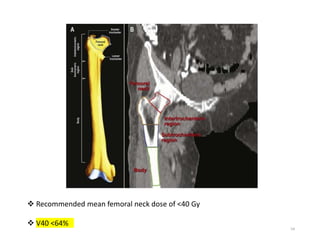

 Recommended mean femoral neck dose of <40 Gy

 V40 <64%

• V40 <64%, Dmean <37Gy, Dmax <59Gy